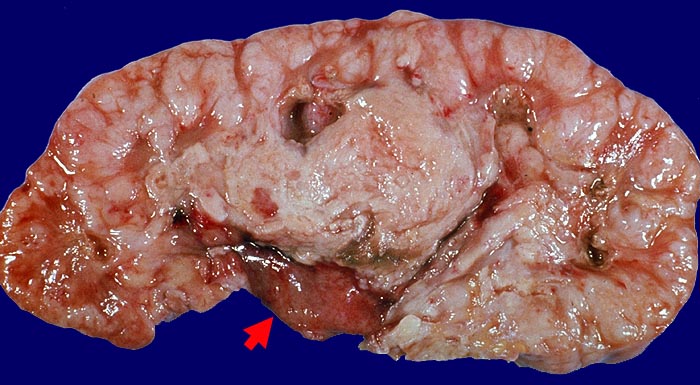

Morphologische Merkmale:

• Solider Tumor mit fokalen Entzündungsinfiltraten.

• Polymorphe Tumorzellen mit unscharfen Zellgrenzen und bläschenförmigen (=vesikulären) Kernen.

• Zahlreiche Mitosen.

• Ureter mit verdickten Kapillaren (Kapillarosklerose).